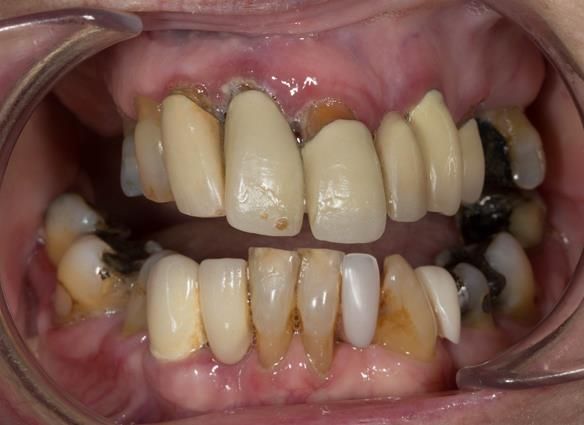

This 73 year old woman was referred to me by her general dental practiioner for treatment.

- “Upper teeth/crowns/bridges all loose”

- “Dentures seem the only option”

- “Bottom teeth are not good but still functional”

- The remaining natural upper natural teeth and lower back molars were heavily restored having generalised periodontitis stage 4 Grade C. Some of the teeth exhibited caries. The prognosis for these teeth ranged from dubious to hopeless.

- The lower teeth (apart from the lower back molars) had better progniosis and were to be managed by the referring general dental practitioner.

- The upper and lower acrylic based partial dentures exhibited suboptimal extension of the flanges and saddles. They had poor retention, support, stability and tissue fit.

- The patient had a high smile line showing 5mm or more alveolar soft tissue above the upper front teeth during social interaction.